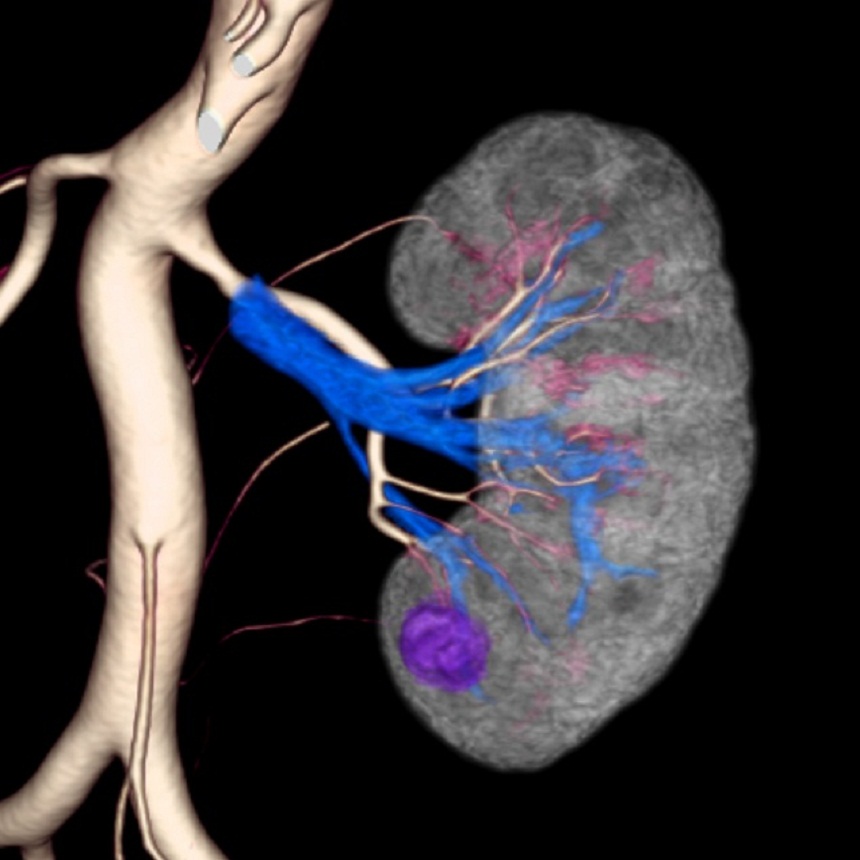

血管撮影とは体表に近い鼠径部や肘窩部などの動脈・静脈からカテーテル(細い管)を入れて、透視画像を見ながら、目的の血管までカテーテルを挿入します。そこから造影剤を注入して撮影を行い、『血管の走行や状態』、『腫瘍の大きさや広がり』を見て撮影診断や処置治療を行う検査になります。 脳血管撮影による診断と治療 肺 : 肺がん、縦隔腫瘍などの診断 左心カテーテル検査:左心系(左心房+左心室+大動脈+冠動脈)で行われる心臓カテーテル検査全般 冠動脈(心臓を栄養する血管)造影検査 右心カテーテル検査:右心系(右心房+右心室+肺動脈)で行われる心臓カテーテル検査全般血管撮影検査について

当院では、心臓血管撮影装置が1台と頭部・腹部血管撮影装置が1台が導入されています。

以下のような病気に対して診断や治療を目的とします。

※血管性の病気

動脈瘤・脳梗塞・心筋梗塞・動脈や静脈の狭窄・消化管などからの出血など

※腫瘍性の病気

肝臓・膵臓 : 肝硬変、肝腫瘍、門脈圧亢進症、膵腫瘍などの診断と治療

その他 :消化管出血、腎臓、泌尿器系腫瘍などの診断と治療